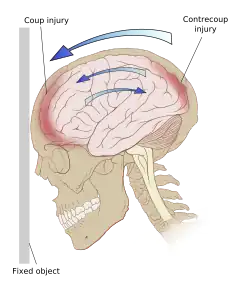

Ricochet of the brain within the skull may account for the coup-contrecoup phenomenon.[65]

Even in the absence of an impact, significant acceleration or deceleration of the head can cause TBI; however in most cases, a combination of impact and acceleration is probably to blame.[37] Forces involving the head striking or being struck by something, termed contact or impact loading, are the cause of most focal injuries, and movement of the brain within the skull, termed noncontact or inertial loading, usually causes diffuse injuries.[20] The violent shaking of an infant that causes shaken baby syndrome commonly manifests as diffuse injury.[66] In impact loading, the force sends shock waves through the skull and brain, resulting in tissue damage.[37] Shock waves caused by penetrating injuries can also destroy tissue along the path of a projectile, compounding the damage caused by the missile itself.[23]

Damage may occur directly under the site of impact, or it may occur on the side opposite the impact (coup and contrecoup injury, respectively).[65] When a moving object impacts the stationary head, coup injuries are typical,[67] while contrecoup injuries are usually produced when the moving head strikes a stationary object.[68]